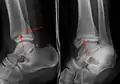

A triplane fracture of the ankle as seen on plain X-ray